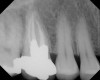

Figure 11  Clinical case of resorption related to the pressure of eruption (a progressive stress) on the upper right lateral incisor.

Figure 11

Figure 12  Clinical case of resorption related to the pressure of eruption (a progressive stress) on the upper right lateral incisor.

Figure 12

Figure 13  Clinical case of resorption related to the pressure of eruption (a progressive stress) on the upper right lateral incisor.

Figure 13

Figure 14  Clinical case of resorption related to the pressure of eruption (a progressive stress) on the upper right lateral incisor.

Figure 14

Figure 15  Clinical case of resorption related to the pressure of eruption (a progressive stress) on the upper right lateral incisor.

Figure 15